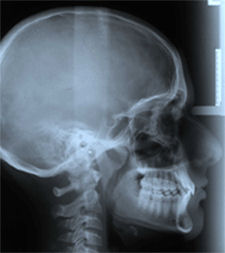

Se presenta el caso clínico de un niño de 10 años de edad, con dentición permanente, tendencia de crecimiento braquicefálico y un patrón esquelético retrognático. Al examen clínico intraoral se evidencia una maloclusión clase II división 1, con un overjet de 8 mm y un overbite de 7 mm. El examen clínico extraoral, evidencia un paciente de perfil levemente convexo, labio superior corto e hipotónico, sonrisa gingival y características faciales asociadas al hábito de respiración bucal. (Fig 1, a-g)

Fig. 1 (a-g): Paciente de 10 a. de edad, maloclusión clase II división 1